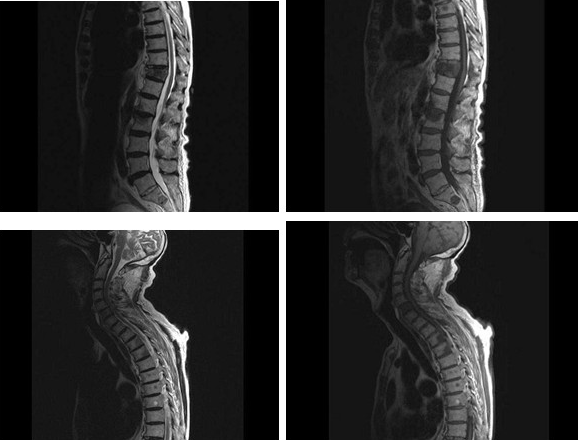

男,87岁,背痛1月余,2月前被诊断为前列腺癌,MRI检查如图,最可能的诊断是()

A . 星形细胞瘤

B . 脊髓空洞症

C . 神经胶质瘤

D . 脊膜瘤

E . 脊椎转移瘤